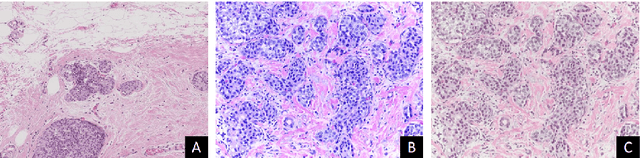

Abstract:Convolutional neural networks (CNNs) have been recently used for a variety of histology image analysis. However, availability of a large dataset is a major prerequisite for training a CNN which limits its use by the computational pathology community. In previous studies, CNNs have demonstrated their potential in terms of feature generalizability and transferability accompanied with better performance. Considering these traits of CNN, we propose a simple yet effective method which leverages the strengths of CNN combined with the advantages of including contextual information, particularly designed for a small dataset. Our method consists of two main steps: first it uses the activation features of CNN trained for a patch-based classification and then it trains a separate classifier using features of overlapping patches to perform image-based classification using the contextual information. The proposed framework outperformed the state-of-the-art method for breast cancer classification.